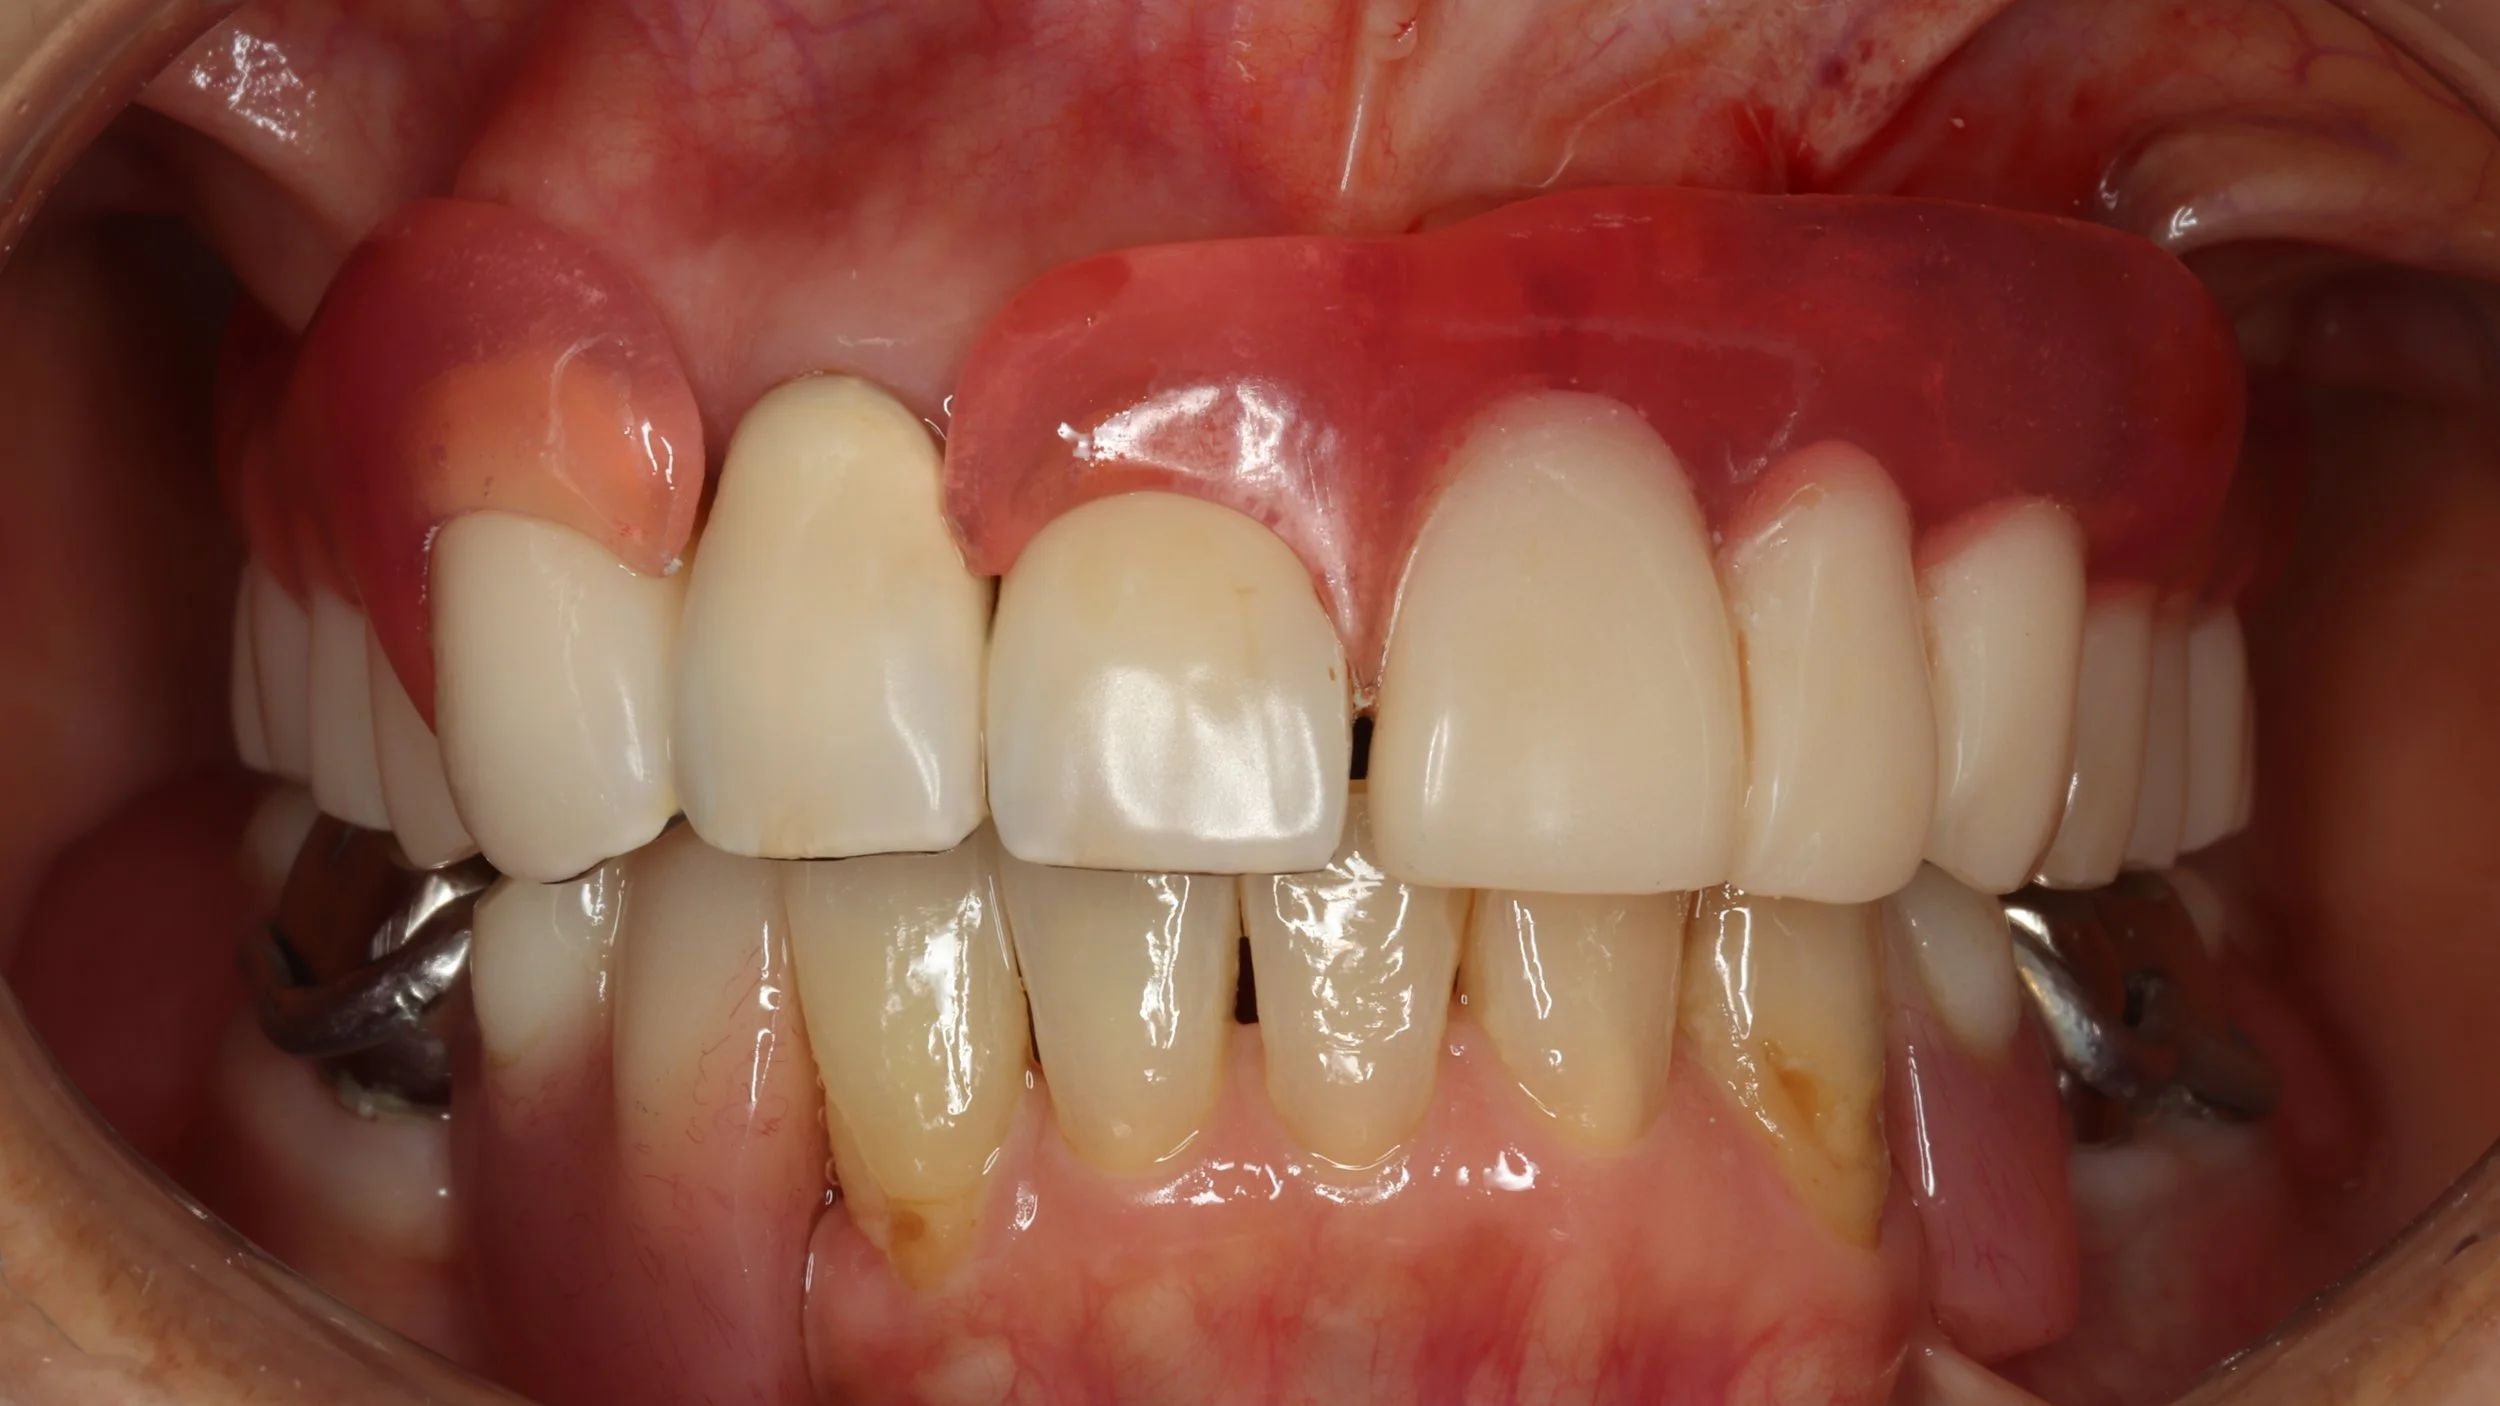

初診時

上の前歯の根はすでに割れており抜歯の必要がありました。抜歯了承後、入れ歯のためのデジタルでの型取りを行いました。

2回目

今回はできるだけ薄く作りたいという希望もあったことから、金属床を用い製作、前歯の抜歯とともに同日に新しい入れ歯を装着。

デジタルデンチャー

奥の歯には、金属で入れ歯を止めるバネを製作し、前歯の見える部分には、透明なレジンクラスプを使用しました。